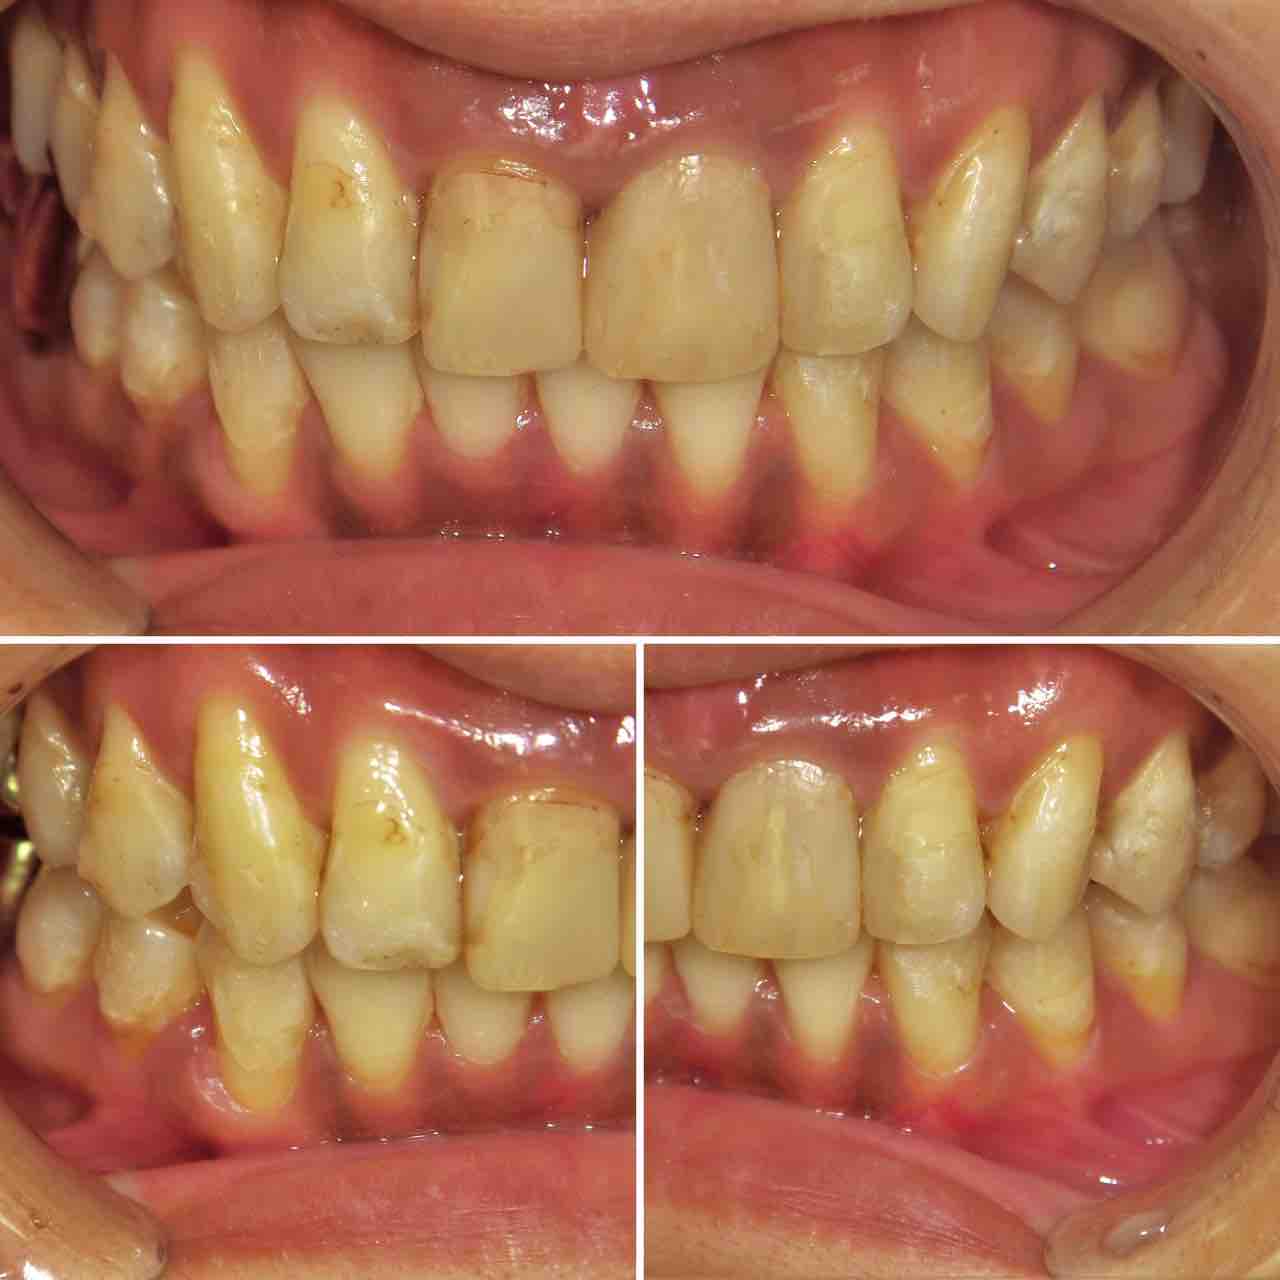

インビザラインで治療を終了した10代の患者さんのケースをご紹介する。

2024年4月5日に治療をスタートした。

内側に引っ込んだ歯を治したいという希望だった。

上の歯。前歯に内側に引っ込んだ歯がある。

下の歯にも同様に引っ込んだ歯がある。

横から見ると少し前歯が出っ歯気味になっている。